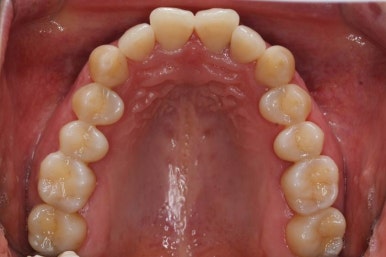

마찬가지로 부산설측교정 키다리아저씨치과에서 처음 내원하셨을 당시의 입안 모습입니다.

어금니쪽은 특별히 이상이 없었고, 위아래 앞니만 삐뚤한 상태였습니다.

이번 환자분은 앞니쪽의 삐뚤한 것만 개선되면 되었기 때문에 부분교정으로 하기로 하였습니다.

부분교정 때 중요한 것은 어금니에는 장치를 부착하지 않고 움직이지 않기 때문에 부분교정으로 개선할 수 없는 경우도 있을 수 있습니다.